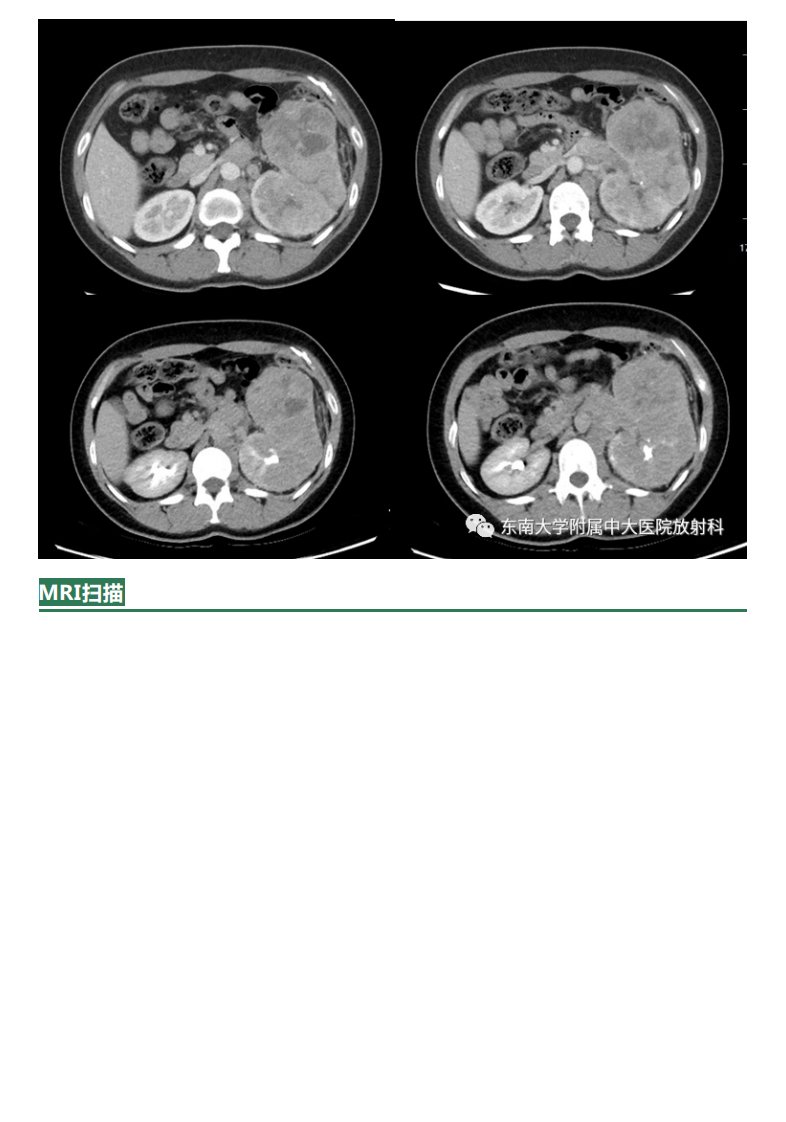

20210622_2【晨读结果公布】2021.06.22泌尿系统疾病——Xp11.2易位TFE3基因融合相关性肾癌.pdf